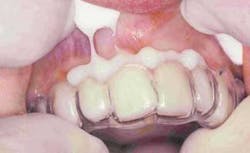

The hard/soft matrix was seated over the prepared teeth to verify fit. Hemaseal & Cide (Advantage Dental Products) desensitizing agent was then used to coat the prepared teeth. After filling the matrix with Pro Temp Garant III autocure bis-acryl temporary crown and bridge material in shade B1, the matrix was seated over the teeth with firm pressure until the resin completely set (Figure 16). The outer hard matrix was first removed, then the inner soft matrix was peeled off to reveal a smooth, polished resin surface with minimal excess resin. The double layer of soft and hard construction allows for superb adaptation of the matrix. This results in temporaries with correct tooth contours, fine margins, and nearly ideal occlusion that require very little trimming and polishing (Figure 17). The minor adjustments can be made with fine polishing diamonds and discs.

The most important step of the temporization process is follow-up. This is the time to evaluate the contours, incisal edge position, color, and verify the patients' choice of smile design in their mouths using their temporaries. Therefore, for every cosmetic case, I see the patient for a follow-up appointment and complimentary cleaning and discuss any comments on shape and length. If any adjustments are needed, they are made with polishing discs. It is far better to catch and make any changes at this point than to have to redo a case. A quick alginate impression poured up in stone can be forwarded to the laboratory for any changes in the final porcelain restorations. Having verified shape and length, occlusion, and phonetics with your temporaries, the next step is to deliver the dazzling smile she desires!